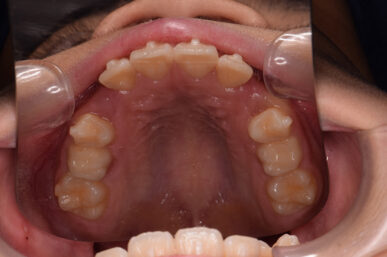

• Before

治療開始が遅くてこのままでは犬歯の生えるスペースが不足していて八重歯になるところでしたが、アライナー矯正で素早く歯を動かして犬歯が生えてくるスペースを作ることで八重歯にならずに済みました。

八重歯のケースは永久歯の抜歯が必要になることもありますが、避けることができました。

矯正後は永久歯がすべて生えるまでは予防歯科で歯の生え代わりと機能を管理します。